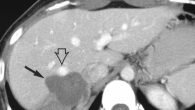

Эхографические признаки патологий

На патологию может указывать повышенная эхогенность и неоднородная эхоплотность. Такие признаки подразумевают серьезные болезни печени: цирроз, гепатит, жировой гепатоз. В таком случае необходима биопсия дефектных участков паренхимы. Только так врач сможет точно определить причину проблемы. Если же проявления повышенной эхогенности комбинируется с очаговыми воспалениями, это указывает на абсцесс, гематомы или метастазы в печени. Такие процессы иногда указывают на лимфому.